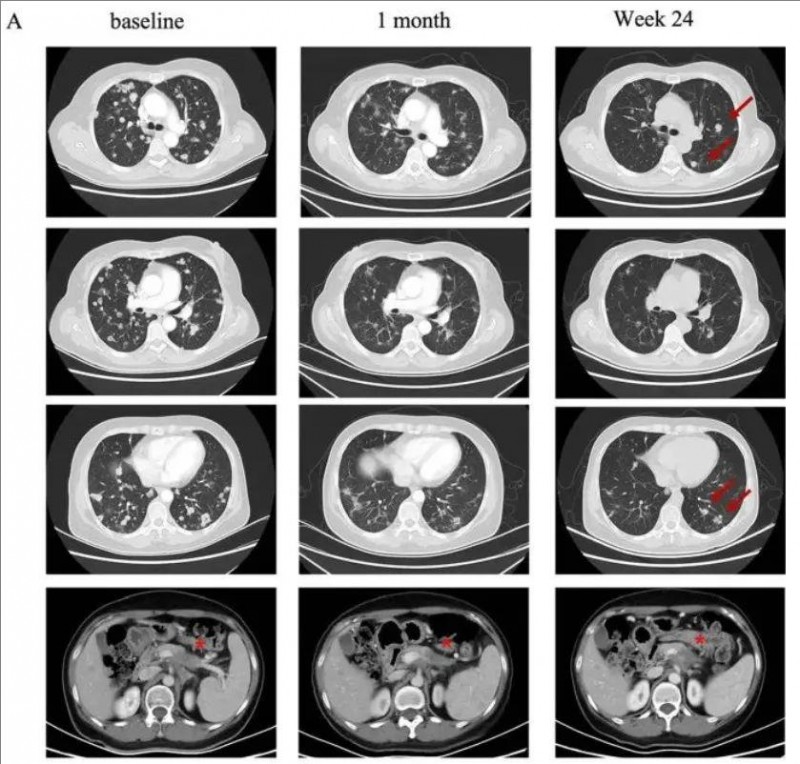

2023年9月21日,科济药业宣布该公司自主研发的靶向Claudin18.2的CAR-T细胞CT041治疗转移性胰腺癌的两个病例报告已发布在9月9日的《血液学与肿瘤学杂志》期刊上。

值得一提的是,这两则典型病例很具有代表性,全部都是化疗失败、全身转移、经历过一二线治疗失败的难治性胰腺癌患者。在参加实体瘤CAR-T疗法CT041临床试验后,均得到不同程度的肿瘤病灶大幅度缩小,甚至完全消失!再次印证了这款里程碑式CAR-T疗法的惊艳疗效!

▲截自《Journal of Hematology & Oncology》

典型病例1

一名58岁的女性胰腺癌患者,伴有肺及淋巴结转移。该患者先后经历一线白蛋白紫杉醇联合吉西他滨和二线伊立替康联合5-氟脲嘧啶治疗后失败。经检测其Claudin18.2表达为2+/70%后入组CT041临床试验。

在进行氟达拉滨、环磷酰胺、白蛋白紫杉醇方案清淋预处理后,患者于2021年9月接受CT041细胞输注。输注后患者出现2级细胞因子释放综合征(CRS),在接受托珠单抗后恢复。根据RECIST v1.1标准,患者肿瘤评估达到部分缓解(PR),肺部转移灶明显缩小。

典型病例2

一名75岁的高龄女性胰腺癌患者,于2019年5月接受了手术切除,诊断为pT2N0期胰腺癌。术后随访5个月时发现肺转移。自2019年12月开始一线S-1单药化疗,在行手术野姑息性放疗期间肺部转移。经检测其Claudin18.2表达为3+/60%后入组CT041临床试验。

在进行氟达拉滨、环磷酰胺、白蛋白紫杉醇方案清淋预处理后,患者于2021年7月输注CT041细胞输注。输注后患者出现2级CRS,经托珠单抗治疗后恢复。患者在CT041输注后第4周进行首次肿评即达到部分缓解(PR),后肺部靶病灶进一步消失达到完全缓解。截至2023年7月末次随访时患者仍处于持续缓解状态。

权威肿瘤专家表示:此次CT041的初步数据显示,CAR-T疗法对胰腺癌的治疗具有相当大的潜力,即使是对既往多种治疗方案失败的患者也是如此。希望CT041在将来有可能改变胰腺癌和其他实体瘤的治疗格局,让我们拭目以待!